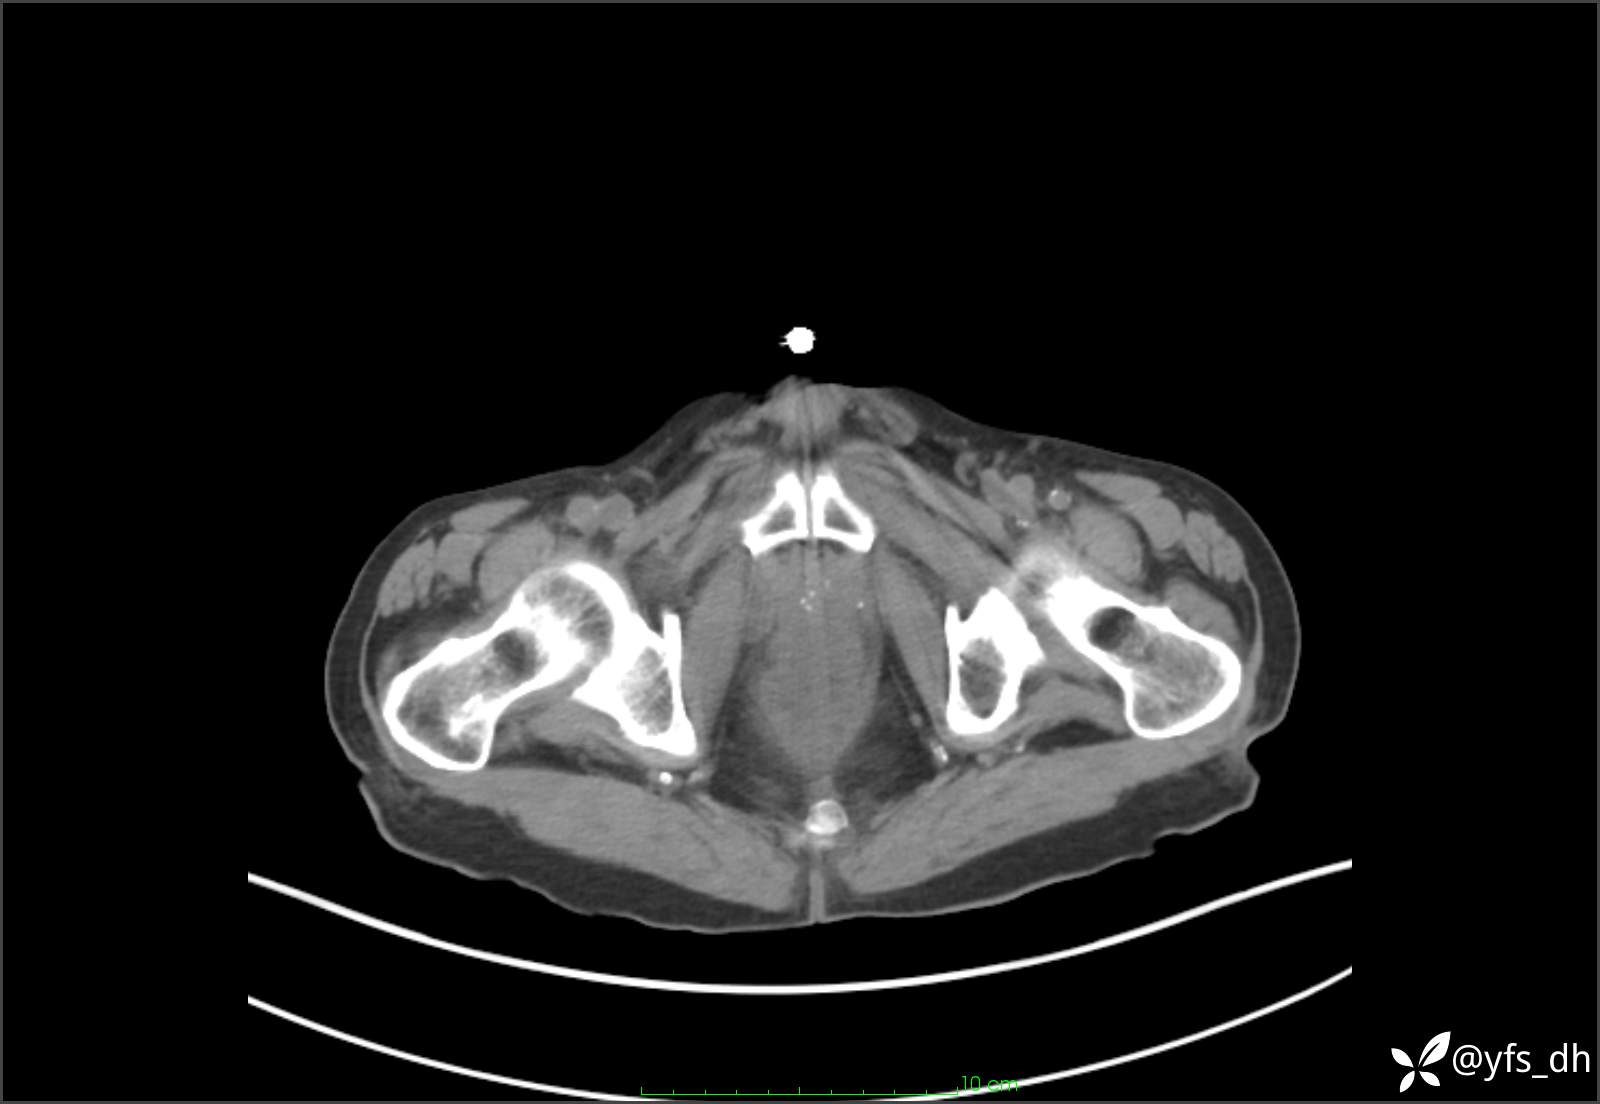

1.简要病史:患者4天前突发上腹部疼痛不适,但可以忍受。3小时前饭后突然加重,不能忍受后就诊。

2.简要手术记录:术中见腹盆腔大量肠液及粪便,乙状结肠中下段见一约3cm的破口。